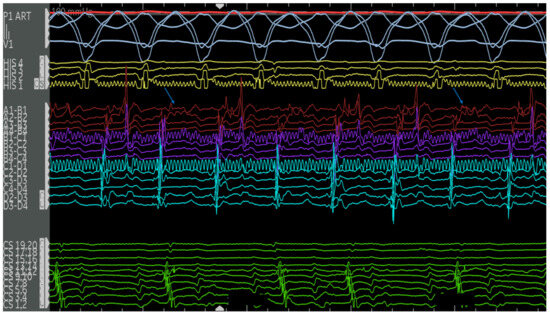

4.2.1. Cases

4.2.2. Case 1

4.2.3. Case 2